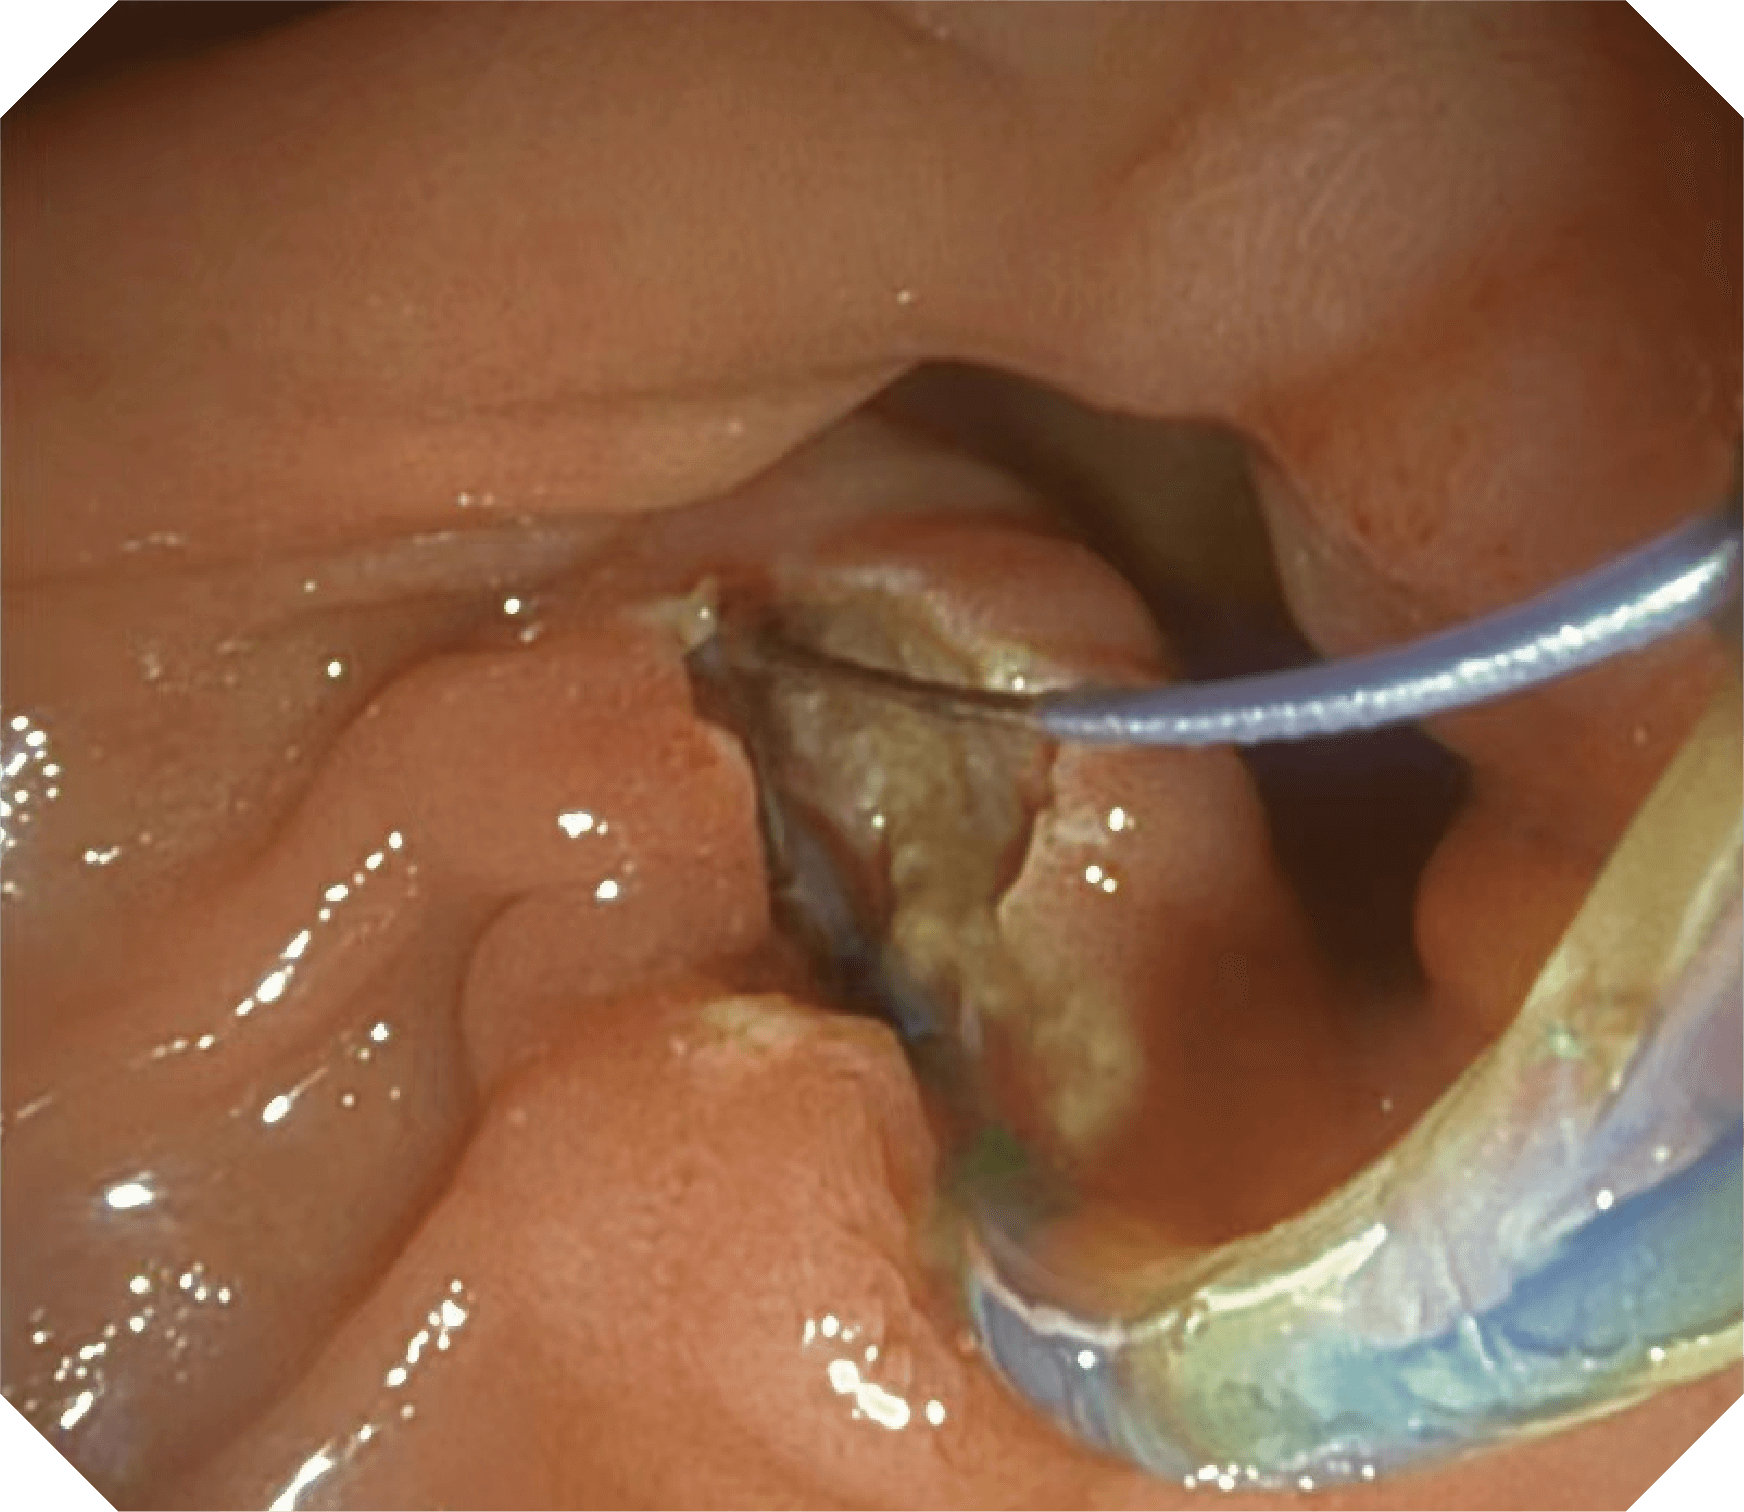

导丝机械锁紧功能

V槽设计提升导丝控制

• 器械辅助导向功能

当切开刀伸出视野外时,导向面引导其回归视野